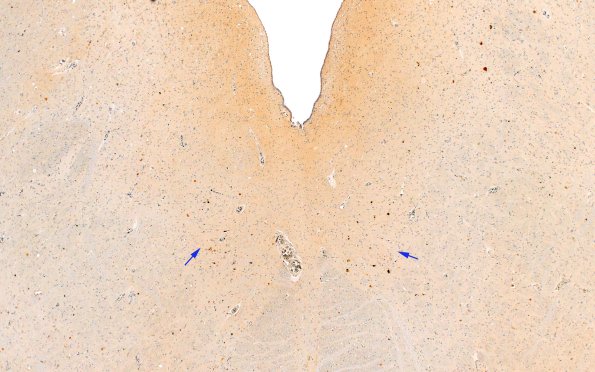

18D1 ALS (Case 18) N8 TDP43 2X copy

18D1-3 There is strong staining of hypoglossal neurons with TDP43.